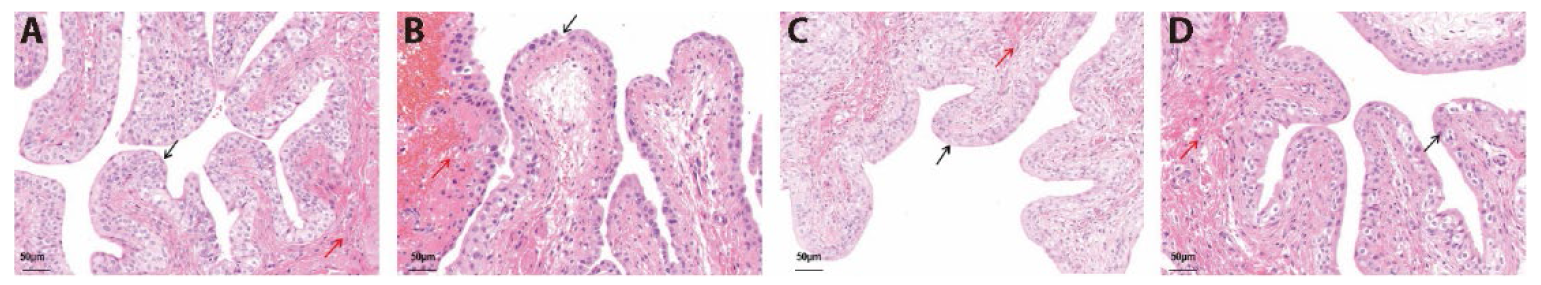

Figure 2 Bladder urothelium tissue structure [HE staining of the bladder wall (×20)] A: control; B: Model; C: EA; D: HC-067047. Control: no modeling or treatment was administered; Model: a single intraperitoneal injection of 2.5% cyclophosphamide (150 mg/kg) without any treatment. EA: EA treatment once daily for three consecutive days after molding. HC-067047 (TRPV4 antagonist): HC-067047 (0.2 mL/time) was instilled into the bladder for 3 consecutive days after molding. EA: electroacupuncture; HE staining: hematoxylin and eosin staining; TRPV4: transient receptor potential vanilloid 4.